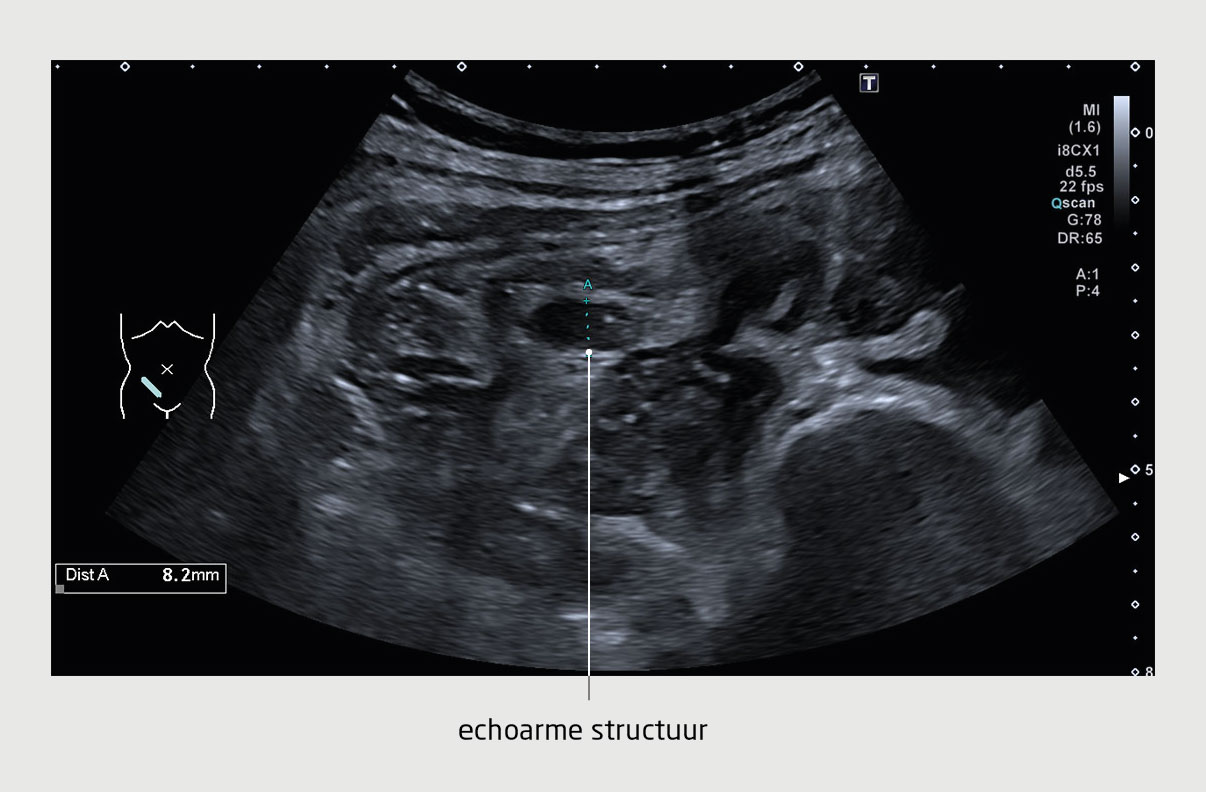

De eerste dag na de laparoscopie persisteerde de pijn en steeg de CRP-waarde naar 222 mg/l. Een CT-abdomen werd vervaardigd, waarop een vena-ovaricatrombose aan de rechterzijde werd gediagnosticeerd (figuur 3). Aangezien de patiënte borstvoeding wilde geven, kozen wij voor een behandeling met laagmoleculairgewicht heparine gedurende 3 maanden. Twee weken na het begin van de behandeling was de patiënte volledig klachtenvrij. Na twee maanden waren op de CT-scan genormaliseerde veneuze structuren te zien.

Figuur 3

Trombose van de v. ovarica bij een kraamvrouw

Figuur 3 | Trombose van de v. ovarica bij een kraamvrouw

CT met intraveneus contrast van het abdomen van de patiënt (veneuze fase, coronale reconstructie). De rechter ureter is proximaal verwijd, met een versterkt aankleurende wand, omringend vocht en vetinfiltratie in de anterieure pararenale ruimte. De v. ovarica is uitgezet, met een centrale hypodensiteit of contrastuitsparing, wat past bij trombose. De conclusie is dat dit het beeld is van een ureteritis in reactie op een vena-ovaricatrombose rechts.